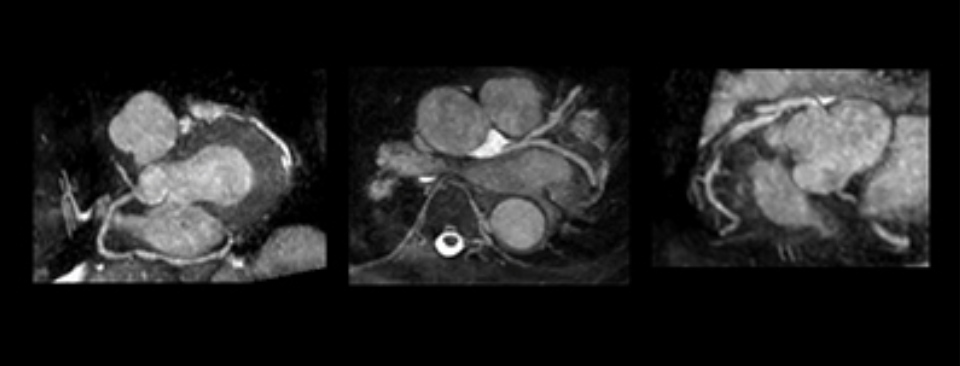

"We leren steeds meer over de invloed van de presentatie van een patiënt op de verwachte resultaten", zegt Dr. Lang. "De linkerhelft van het hart vormt het primaire aandachtsgebied bij het beoordelen van deze patiënten, maar in het zorgtraject voor patiënten met COVID-19 is het belangrijk om naar beide kanten te kijken. Tools voor het automatisch bepalen van de strain hebben de beoordeling van de rechterventrikelfunctie vereenvoudigd, wat belangrijk is voor hun zorg."

60%-65% van de gevallen van COVID-19 waarbij het hart is aangedaan, gaat gepaard met een bepaalde mate van problemen met een linkerhartkamer disfunctie.”

Wat is de impact van het COVID-19 virus op de linker- en rechterhelft van het hart? Lees meer in deze whitepaper met Dr. Roberto Lang van de Universiteit van Chicago. Geen zin om te lezen? Bekijk dan het tweedelige video interview hieronder (25 min).